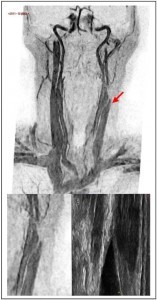

At 1 year follow up the EDSS was 3 again and the patient reported recurrent fatigue that she had been experiencing for several months. Further investigation revealed a CCSVI related left IJV tandem obstruction. At mid cervical level B-mode color Doppler demonstrated an IJV obstruction mirrored by an MRV imaging. In both cases a pencil tip pencil sign was demonstrated (Figure 2). The color Doppler assessment highlighted a left IJV dynamic flow obstacle caused by an extrinsic compression (Figure 2), that could be relieved by yawning.

At the caudal level a color Doppler detectable blocked outflow was demonstrated. The flow abnormality was linked to a M-mode evident fixed valve leaflet.

Considering a further PTA pointless, an open surgical access was placed. The macroscopic evidence of the extrinsic stricture, caused by a fibrotic and short OM intermediate tendon on the IJV, lead to the surgical transection of the two muscular bellies. In addition, endophlebectomy of the terminal IJV permitted the removal of a fibrotic septum. The procedure was completed by patch angioplasty by using an autologous great saphenous vein. The patient tolerated the procedure well and neither major nor minor complications were reported.